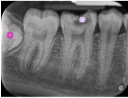

Periapical 5